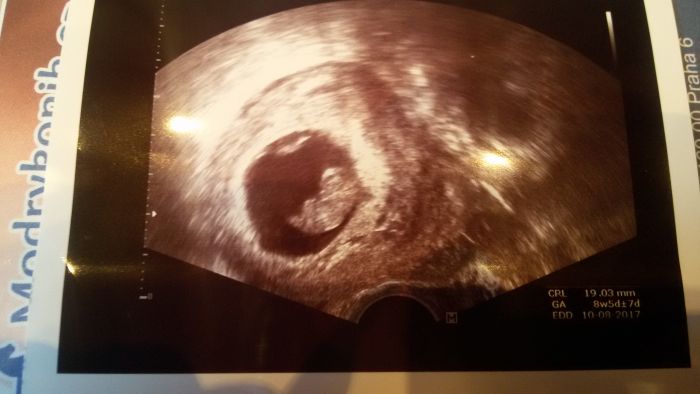

miminko dohnalo ztrátu a odpovídá i podle UTZ 9+4, srdíčko pulsuje a měří 2,7cm